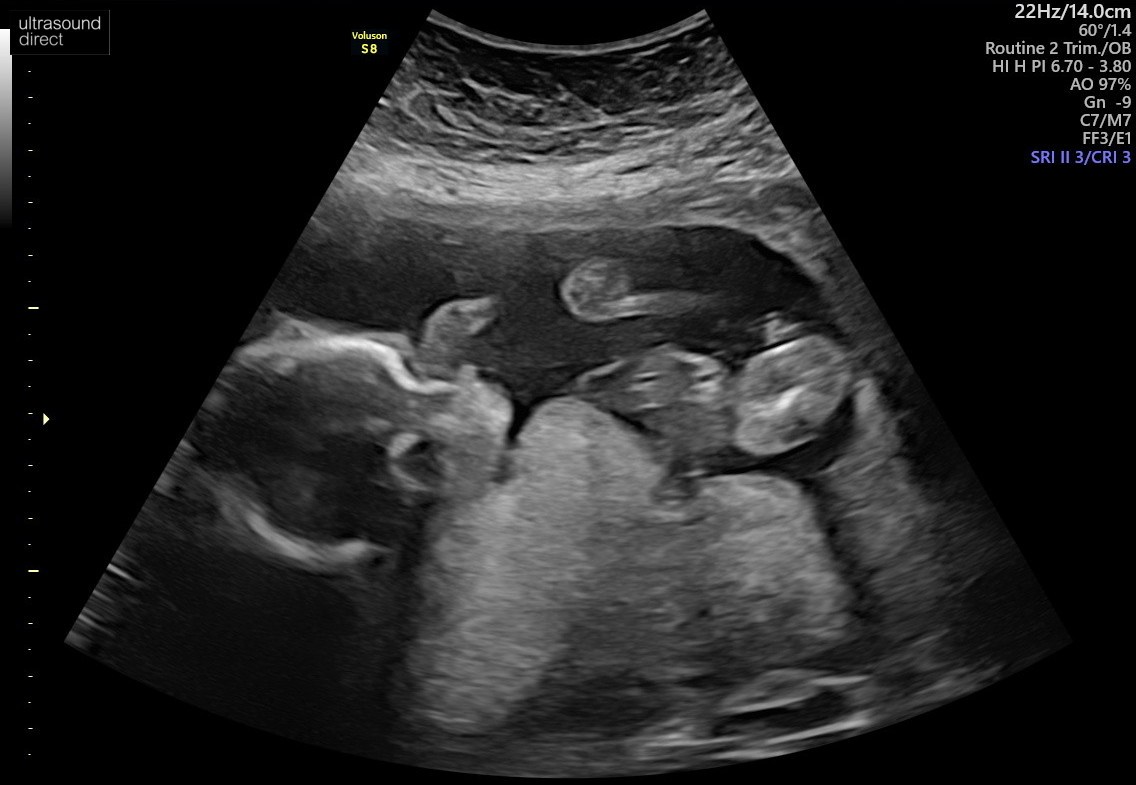

Wg mnie wygląda to na dziecko...Witajcie

Może sprawne oko którejś mamusi podpowie czy po tym rozmazanym USG można stwierdzić płeć maleństwa![]()

Nie da się stwierdzić płci po tych zdjęciach... A lekarz nic nie powiedział?Witajcie

A mi pani doktor powiedziała "dziewczynka" a pan doktor na prenatalnych "chłopiec"Wg mnie wygląda to na dziecko...

Poważnie, jak lekarz nie powiedział płci to losowe osoby z forum powiedzą.

A jak powiedział płeć to możesz mu zaufać lub powtorzyc badanie u innego specjalisty.

Wystarczy zaczekać do kolejnej wizyty i zapytać. A jak się niecierpliwisz to zadzwoń i niech sprawdzą w karcie jaka płeć.Nie chodzi tu o brak zaufania do lekarza tylko o to, że w dniu USG mamusia nie chciała znać płci dziecka.

Ciekawość jednak wzięła górę

I wiem, że lekarzami nie jesteśmy (przynajmniej w większości) więc nie ma co się spinać. Za to są tu mamy z różnym doświadczeniem i na ich opinię liczę![]()